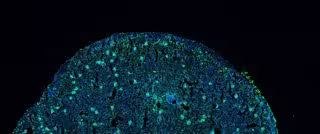

Aparición de inmunocomplejos en el riñón (en verde). / - ANDRÉS PARÍS-MUÑOZ, CNB-CSIC.

Los investigadores han estudiado la expresión de una proteína llamada Helios, que, cuando se encuentra en bajos niveles en el interior de los linfocitos, podría indicar la presencia de lupus. Ahora, el equipo del CSIC ha analizado la expresión de Helios en diferentes tipos celulares de modelos animales y han identificado diversos marcadores diagnósticos que describen parámetros de la enfermedad.